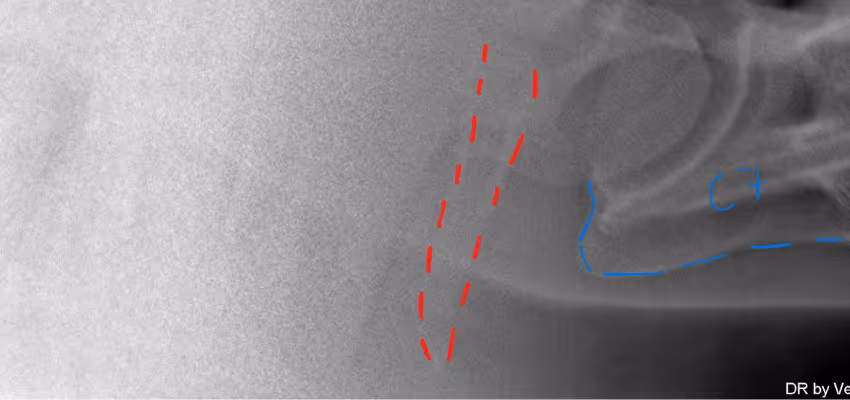

Bildgebende Verfahren (Röntgen, MRT, CT)

Röntgenaufnahmen, MRT und CT-Scans sind entscheidend für die Diagnose von ECVM. Diese bildgebenden Verfahren ermöglichen es, Fehlbildungen der Wirbelsäule sichtbar zu machen.

Elterntiere in der Zucht mit Bedacht wählen

Zuchtstrategien spielen eine wichtige Rolle bei der Vermeidung von ECVM. Durch gezielte Auswahl von Zuchttieren können genetische Risiken minimiert werden. Durch Röntgenbilder lassen sich mittlerweile die Malformationen der Halswirbel gut darstellen. Da eine genetische Veranlagung der Knochenveränderungen ECVM vermutet wird, ist es durchaus sinnvoll, die Gesundheit beider Elternteile zu überprüfen.

ECVM ist eine komplexe Halswirbelsäulenerkrankung bei Pferden, die hauptsächlich genetische Ursachen hat. Eine frühe Diagnose und gezielte Behandlungen können die Lebensqualität betroffener Pferde erheblich verbessern. Vor allem bildgebende Verfahren spielen eine wichtige Rolle beim Erkennen der Krankheit eine wichtige Rolle.